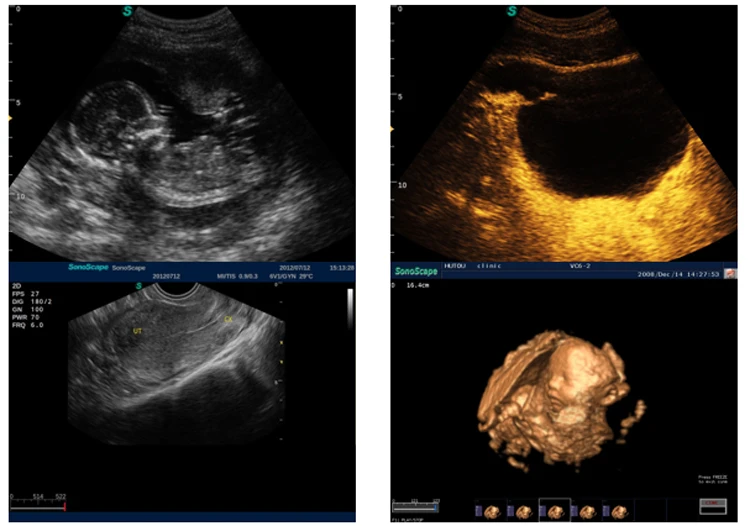

The S2 is configured with comprehensive functions, including complete scanning modes, such as outstanding 2D performance, sensitive blood flow, and 3D/4D imaging technology. The S2 is endowed with the best functions in its class! The scanning modes include B /2B/4B/M/ Steer M/Color/DPI/PW/ CW.